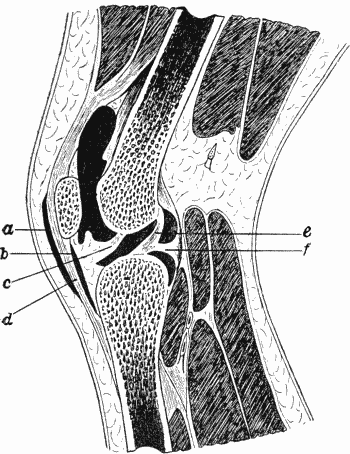

80.Section of Knee-joint showing Extent of Synovial Cavity156

122.Tuberculous Synovial Membrane of Knee230

123.Lower End of Femur from an Advanced Case of Tuberculous Arthritis of the Knee231

124.Advanced Tuberculous Disease of Knee, with Backward Displacement of Tibia233